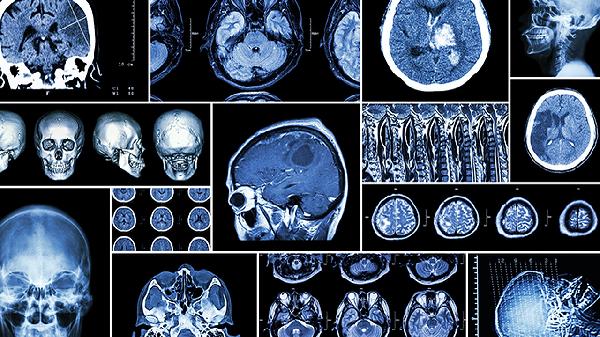

小头畸形手术是针对颅骨发育异常患儿进行的颅腔扩容或颅缝重建手术,主要适用于颅缝早闭、脑发育受限等病理类型。手术方式包括颅缝切开术、颅骨重塑术、额眶前移术、颅腔扩容术及分阶段矫正术五种。

通过植入可扩张钛网或生物材料增加颅腔容积,适用于脑组织持续生长的低龄患儿。分阶段手术间隔4-6个月,需定期CT评估脑室变化。该方法对脑代谢异常导致的小头畸形效果有限。

术后护理需重点关注头围增长曲线、神经发育评估及颅内压监测。建议每3个月复查头颅CT或MRI,配合康复训练促进运动功能发育。日常避免头部碰撞,保证每日30-50μg维生素D摄入促进骨愈合。母乳喂养患儿母亲需补充足量钙质,配方奶喂养者选择高热量强化配方。出现呕吐、嗜睡等颅高压症状需立即就医。